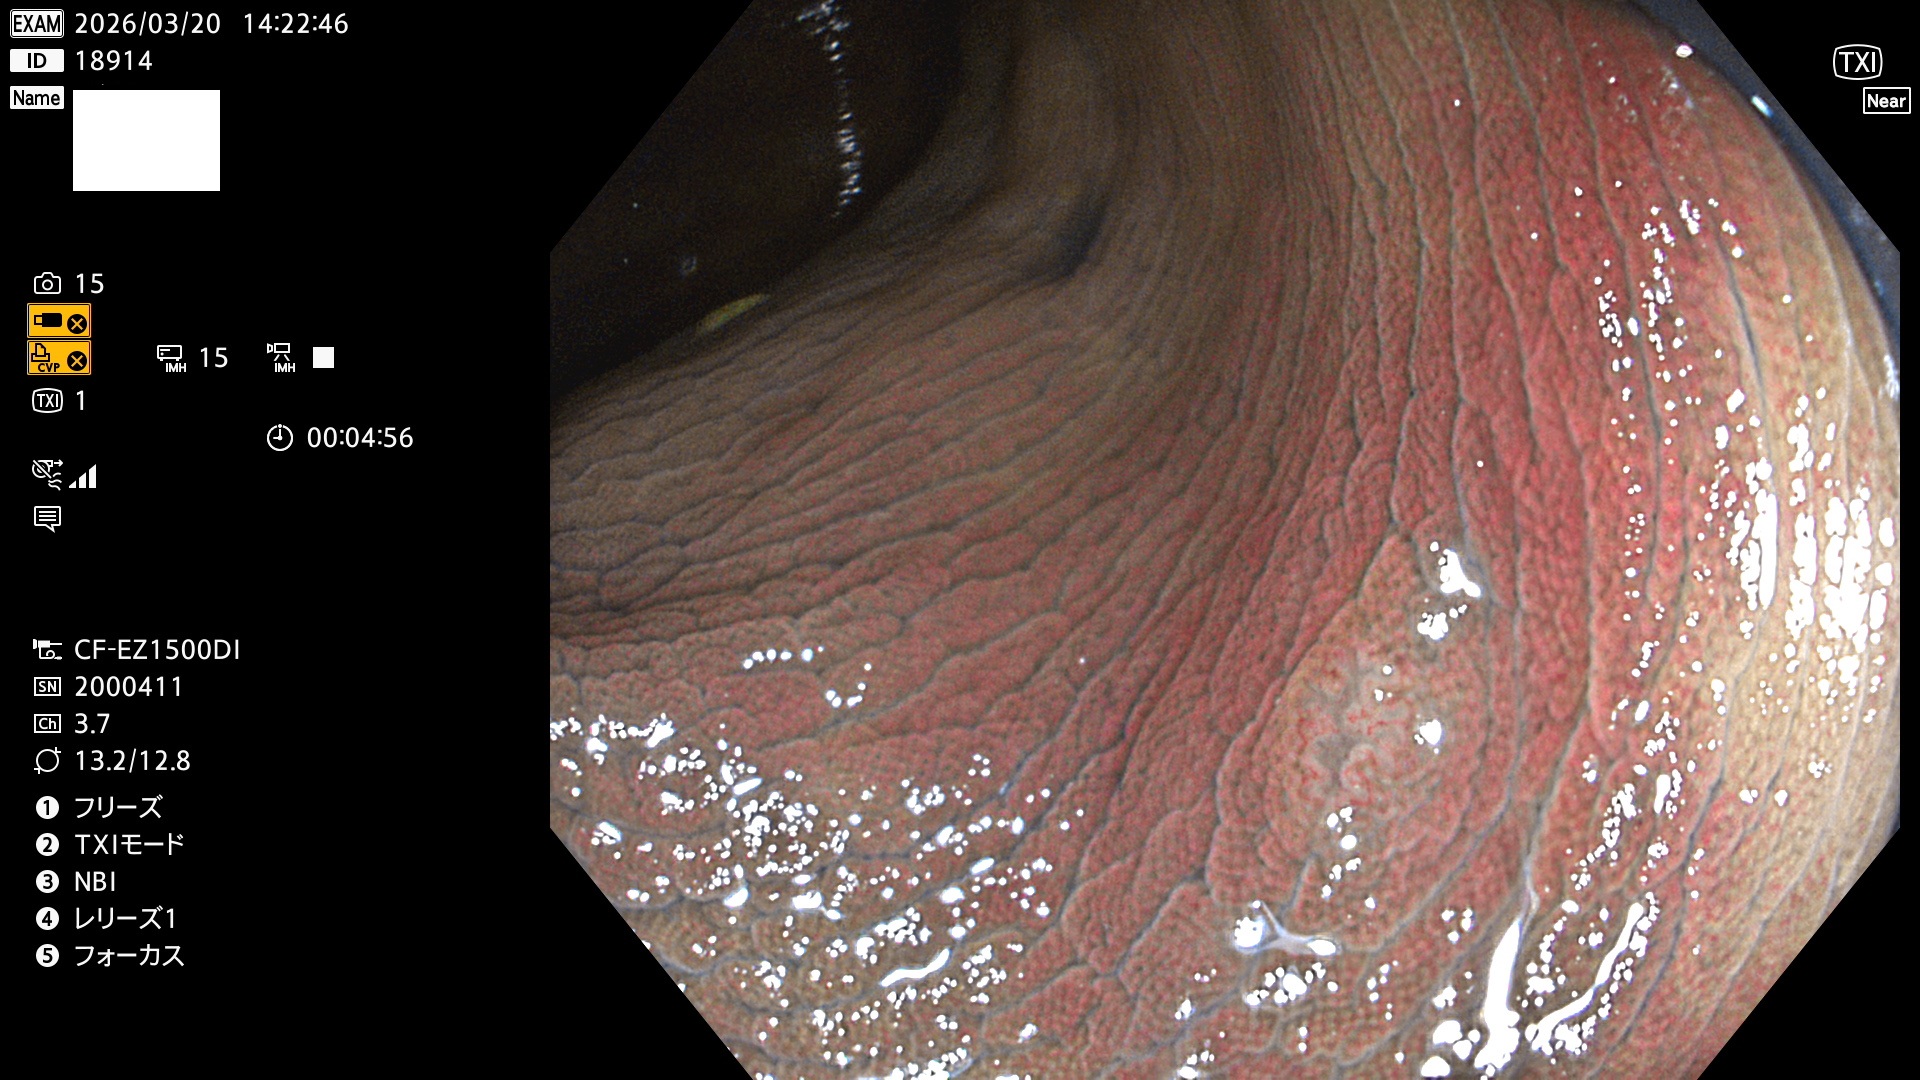

完全に平坦な物をUb、陥凹している物をUcと呼びます。Ubは認識が困難で、Ucはびらん(炎症)と紛らわしいために見落とされやすく、「内視鏡後・大腸癌」の原因になります。

毎週の検査(木・金・土・日)に発見されたUbとUc型・腺腫を、その週の日曜の夜にUPし1週間、提示します。

2026年3月19日〜3月22日の4日間(40件)4個 (Uc_ADR=4個/40人=10%)